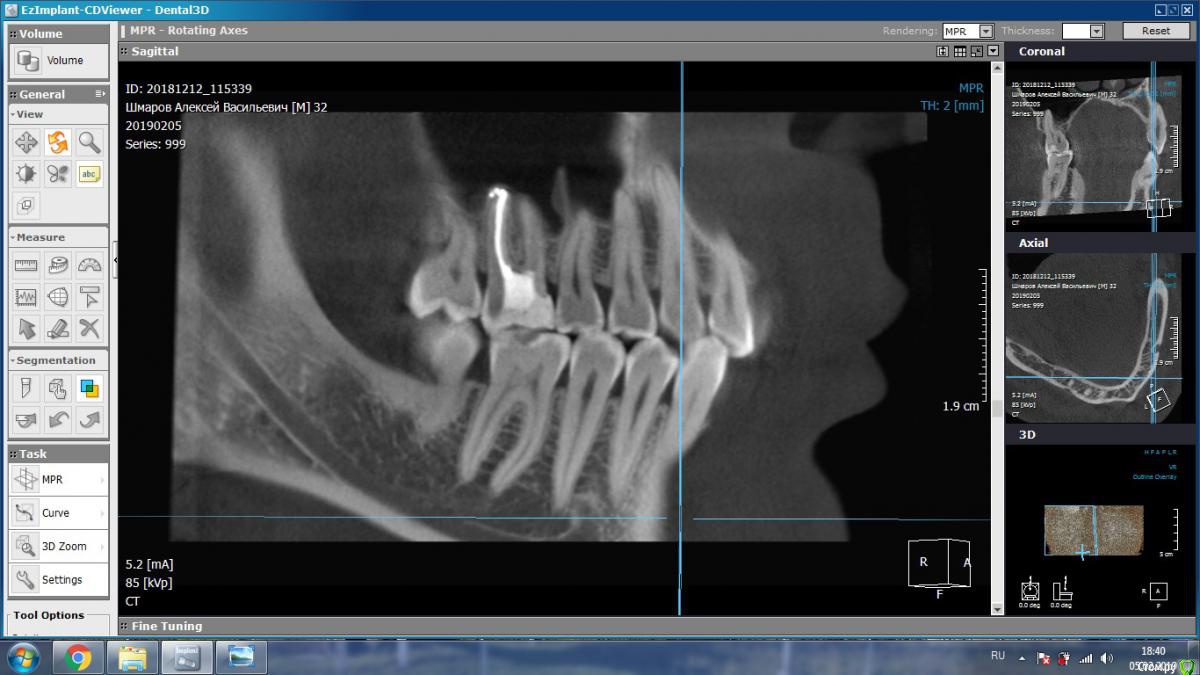

aleks.k Опубликовано 5 февраля, 2019 Автор Поделиться Опубликовано 5 февраля, 2019 Добрый день! Сделал КТ. Посмотрите пожалуйста.Есть 2 мнения очных стоматологов, пока никто из них КТ не видел, мнение на основании предыдущего панорамного снимка:1. Надо удалять 6 зуб справа2. Который и депульпировал 6 зуб сказал, что проблемы в 6 зубе нет, зуб мудрости нужно оттянуть брекетами. Размер файла 131 мб. http://fayloobmennik.cloud/7349278 Ссылка на комментарий

aleks.k Опубликовано 5 февраля, 2019 Автор Поделиться Опубликовано 5 февраля, 2019 Такие подойдут? Ссылка на комментарий

kramer Опубликовано 5 февраля, 2019 Поделиться Опубликовано 5 февраля, 2019 Судя по срезам, вероятнее причина в пульпите 7 зуба, возникшего в результате давления на него 8-ки. Ссылка на комментарий

aleks.k Опубликовано 6 февраля, 2019 Автор Поделиться Опубликовано 6 февраля, 2019 Срезы Ссылка на комментарий

aleks.k Опубликовано 6 февраля, 2019 Автор Поделиться Опубликовано 6 февраля, 2019 Еще один срез, может быть более удачный чем первые в этой проекции Ссылка на комментарий